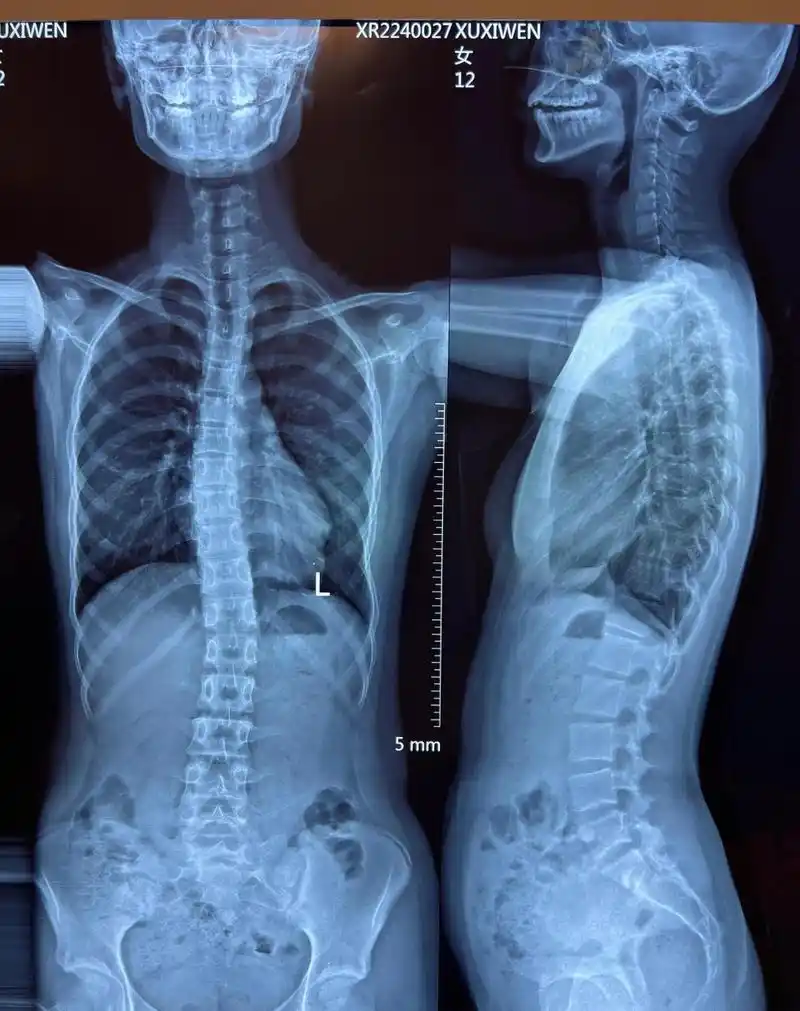

"医生,您不知道,我孩子的学校是西安的重点中学,作业太多了,根本